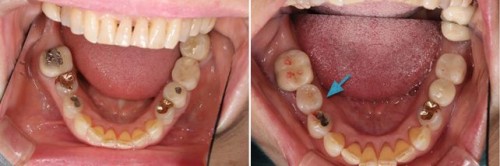

術前術後です。奥歯の銀歯が気になるとの患者様でしたが、このようにセラミックインレーに変更しましたが、大変喜ばれました。